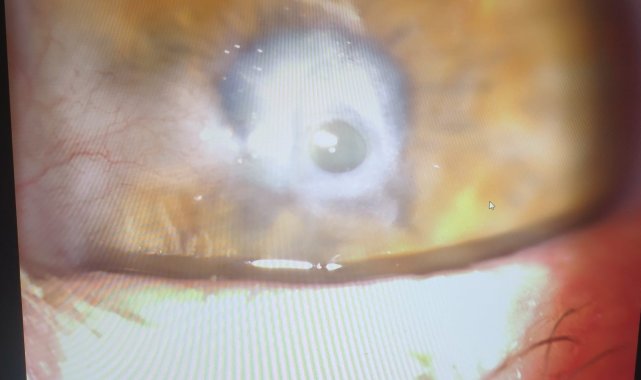

25 yıl önce geçirdiği iş kazası nedeniyle sol gözünde ağır görme kaybı yaşayan hasta, Kastamonu Eğitim ve Araştırma Hastanesi Göz Polikliniği'ne başvurdu. Yapılan muayenede, hastanın korneasının enfeksiyon nedeniyle delinme aşamasında olduğu, kornea üzerinde et büyümesi (pterjium) ve katarakt bulunduğu belirlendi. Tıp Fakültesi Göz Hastalıkları Anabilim Dalı Başkanı Prof. Dr. Firdevs Örnek ile Dr. Öğretim Üyesi Barış Kömür tarafından gerçekleştirilen yaklaşık 2 saatlik operasyonla hastaya aynı anda katarakt ameliyatı, göz içi lens implantasyonu, pterjium temizleme ve kornea nakli yapıldı. Kentte ilk kez gerçekleştirilen kombine katarakt ve kornea nakli ameliyatı başarılı geçti. Ameliyat sonrası hastanın görme kabiliyetini yeniden kazandığı belirtildi.

Nakil ameliyatını gerçekleştiren Dr. Öğretim Üyesi Barış Kömür, "Görmenin sağlanması için kornea ve lensin saydam olması gerekmektedir. Gözün diğer katmanları sağlıklı olmasına rağmen, 25 sene önce iş kazası sonrası sol gözünde ağır görme azlığı, geçirilmiş olan enfeksiyonlara bağlı olarak delinmekte olan kornea ve kornea üzerine yürümüş et (pterjium) ile gelişmiş olan kataraktı bulunan hastada, katarakt ameliyatı ve göz içi lens implantasyonu yapılmasını takiben organ bağışı yapan bir kişiden alınmış kornea başarılı bir şekilde nakledildi" dedi.

Kornea Nakil Merkezi Sorumlusu Dr. Barış Kömür, hastaya nakledilen korneanın Konya'daki göz bankasından temin edildiğini belirterek, "Geçtiğimiz aylarda hastanemiz bünyesinde açılan Kornea Nakil Merkezi sayesinde, uzun zamandır korneasındaki hastalığa bağlı olarak bulanık görme sorunu yaşayan ve travmatik kataraktı olan hastamıza katarakt ile birlikte kornea nakli yapılmasını kararlaştırdık. Gerekli hazırlıkların tamamlanmasının ardından ameliyat başarılı bir şekilde gerçekleştirildi" ifadelerini kullandı.